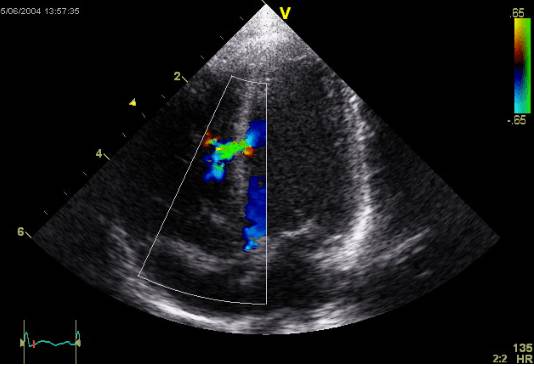

Эхокардиограмма

С помощью такого метода диагностики удаётся понять, какова форма тромба и какой у него размер, где он находится.